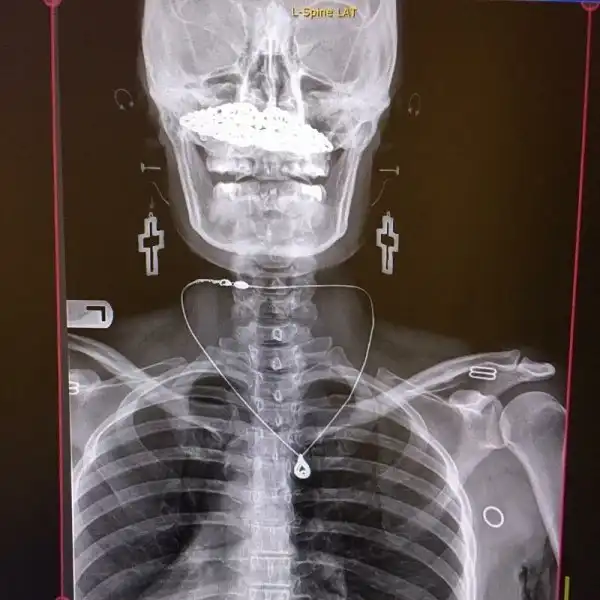

Когда забыл снять пирсинг и украшения